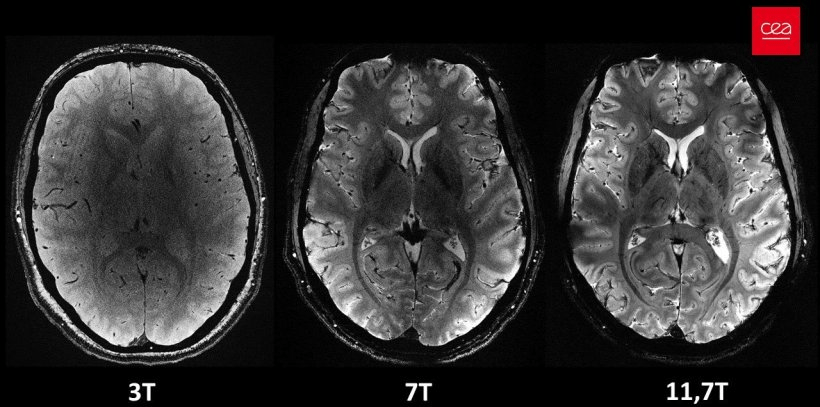

The Best MRI in the World